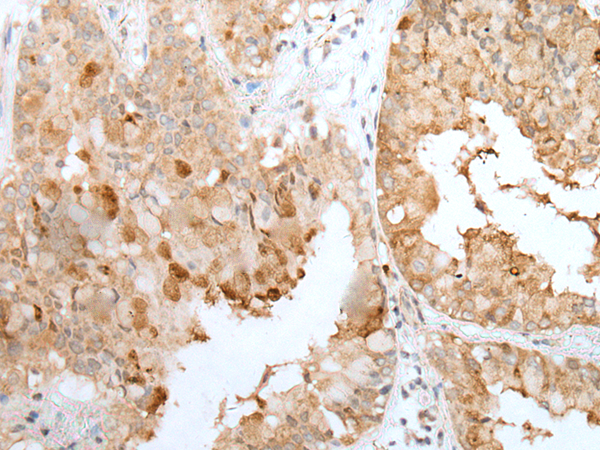

分类: 科研抗体货号: P02443别名: CT3; CT95; CTAG3; bA69L16.7应用: WB,IHC反应种属: Human